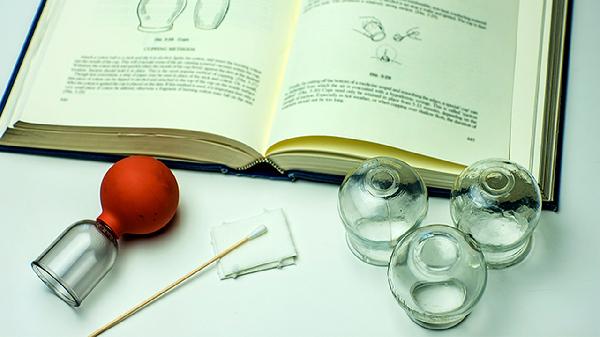

拔罐的禁忌和注意事项

拔罐疗法需避开皮肤破损、出血倾向、严重疾病急性期等禁忌情况,操作时需注意罐具消毒、留罐时间、体位选择等关键事项。1、禁忌人群:皮肤溃疡、湿疹等皮损患者禁用拔罐,避免感染扩散;血友病、血小板减少等出血性疾病患者可能引发皮下出血;妊娠期妇女腰腹部慎用,以免刺激子宫;高热抽搐、心肾功能衰竭等急重症患者禁用。恶性肿瘤局部、骨折未愈合部位同样禁止施术。2、禁忌部位:颈...

拔罐的禁忌 拔罐的原理和禁忌

拔罐疗法通过负压吸附刺激经络穴位,但存在皮肤破损、出血倾向、严重慢性病等禁忌。主要禁忌包括皮肤感染、凝血功能障碍、妊娠期腰腹部操作、空腹或饱食后立即操作、体质极度虚弱五类情况。1、皮肤感染:局部存在疱疹、溃疡、烧伤等皮肤损伤时禁止拔罐。罐体负压可能加重创面渗出,导致继发感染扩散。皮肤屏障功能受损区域操作易引发接触性皮炎,愈合期患者需待表皮完全修复后再考虑拔罐...

拔罐的禁忌 拔罐不适合哪些人

拔罐疗法并非人人适用,皮肤破损者、血液疾病患者、孕妇腰腹部、严重心脏病患者及体质极度虚弱者均属禁忌人群。拔罐禁忌主要涉及皮肤状态异常、凝血功能障碍、特殊生理阶段、心血管风险及体质因素五类情况。1、皮肤破损:局部存在伤口、湿疹、疱疹或烧伤时,负压刺激可能加重皮肤损伤,导致感染扩散。糖尿病患者皮肤愈合能力差,即使微小破损也应避免拔罐。皮肤过敏急性发作期同样不适宜...

拔罐的坏处与注意事项

拔罐疗法可能引起皮肤淤血、水泡、感染等不良反应,操作时需注意体质禁忌与部位选择。主要风险包括局部淤血、皮肤损伤、晕罐反应、感染风险及加重特殊病情,需严格遵循操作规范并避开禁忌人群。1、局部淤血:拔罐形成的负压会导致毛细血管破裂,出现紫红色罐印属于正常现象。但留罐时间过长或负压过大时,可能造成深层组织淤血,表现为皮肤青紫面积扩大且消退缓慢。气血虚弱者更易出现此...